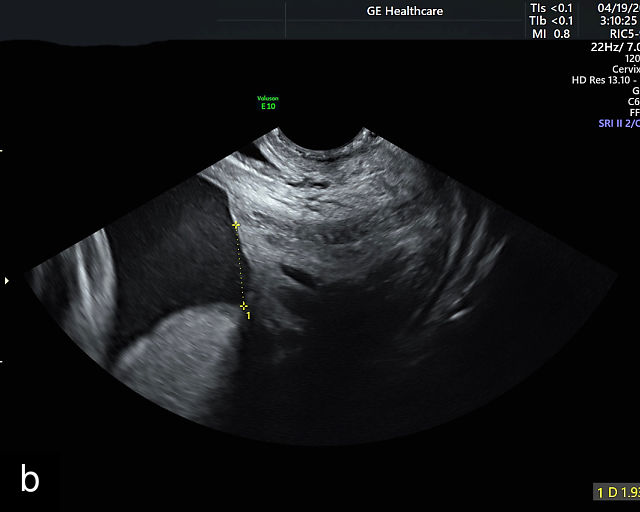

In the past, placenta previa was classified as complete, partial, marginal or low-lying.50,61 However, with advancements in ultrasound technology allowing precise assessment of the relationship between the placenta and the internal cervical os, the classification has been simplified.67 Placenta previa now refers to cases in which the placenta overlies the internal os to any degree, while low-lying placenta describes cases in which the lower placental edge lies within 2 cm of the internal os (Figure 5).51,66,67

5

Placenta previa and low-lying placenta. (a) Transabdominal grayscale ultrasound image suspicious for placenta previa. The placenta (PL) appears to overlie the internal cervical os (CX). Note the time stamp: 2:19:37. (b) Transvaginal ultrasound of the same patient taken approximately 50 minutes later. Note the time stamp: 3:10:25. The internal os and the lower placental edge are both clearly seen, and the placenta does not overlie the internal os. Because the lower placental edge is 1.93 cm from the internal os, it will likely resolve by the third trimester. (c) Transabdominal grayscale ultrasound of placenta previa. The placenta (p) covers the cervix, but the cervix, especially the internal os, cannot be visualized due to shadowing. (d) Transabdominal grayscale ultrasound of placenta previa. The placenta (p) covers the cervix (c) but shadowing obscures adequate visualization. The internal os is indicated by the arrow. (e) False-positive image of placenta previa on transabdominal grayscale ultrasound. The bladder (b) is full, pushing the anterior and posterior walls of the lower uterine segment (ls) together making it appear that the placenta (p) overlies the internal os of the cervix. In reality, the line depicted by the arrowheads is where the anterior and posterior walls of the lower segment are in proximity to each other. The cervix is much lower and is obscured by shadowing (c). (f) Transabdominal grayscale ultrasound image of placenta previa. The placenta (p) covers the cervix (c), but the cervix, especially the internal os, cannot be visualized due to shadowing. b, bladder. (g) Transvaginal grayscale ultrasound image of placenta previa. The placenta (p) completely covers the internal os (arrow) of the cervix (c). The internal os can be seen clearly. h, fetal head. (h) Transvaginal grayscale ultrasound image of posterior low-lying placenta (p). The lower placental edge is clearly seen and is 1.56 cm from the internal os (arrow) of the cervix (c). The placental edge and the internal os are clearly seen. h, fetal head. (i) Transvaginal grayscale ultrasound image of a posterior placenta previa (p). The internal cervical os is clearly seen (arrow). c, cervix. (j) Transvaginal grayscale ultrasound image of an anterior placenta previa (p). The internal cervical os is clearly seen (arrow). c, cervix; h, fetal head. (k) Transvaginal grayscale ultrasound image of a posterior placenta that was thought to be low-lying on transabdominal sonography but could not be adequately assessed. This examination clearly shows the lower edge of the placenta (p) to be 2.18 cm from the internal os (arrow) of the cervix, firmly establishing that the placenta is not low-lying and allowing the patient to undergo labor safely and deliver vaginally. c, cervix. (l) Transvaginal grayscale ultrasound image of placenta previa. The placenta (p) completely covers the internal os (arrow) of the cervix (c). The internal os can be seen clearly.

Most cases of placenta previa will be suspected prenatally by transabdominal ultrasound.49 However, this approach has several limitations and may be inaccurate.72,73,74 because the relationship between the placenta and the internal cervical os may be difficult to assess by transabdominal ultrasound.72,73,74 The bladder may be full, pushing the anterior and posterior walls of the lower uterine segment together, falsely creating the impression of a placenta previa (Figure 5e).61 There may be considerable shadowing, including by the fetal presenting part, which may limit the accuracy of transabdominal ultrasound (Figure 5d,f).75 Posterior placentas may be more difficult to assess.

Transvaginal ultrasound overcomes these limitations (Figure 5g–l).72,73,74,76 The probe is inserted into the vagina and therefore is closer to the region of interest.51,61 In addition, transvaginal transducers have higher frequencies and superior resolution compared to transabdominal transducers. Transvaginal ultrasound is safe and is not associated with increased bleeding.72,73,74,75,76 As such, transvaginal ultrasound should be the imaging modality of choice whenever there is suspicion of placenta previa.49,67,77